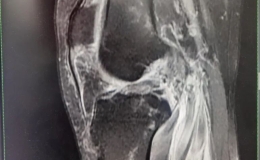

解决“隐形杀手”,重启行动“自由” ——广济医院常规开展关节镜下人工韧带重建术

“骑车摔的,疼得越来越厉害了。”凌晨时分,伴随着呼啸而来的急救车,程女士(化名)被送至广济医院急诊科,初诊后,患者被第一时间送入骨科病房。进一步完善检查,发现患者除头部损伤外,......